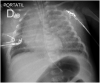

In recent decades there have been multiple pathogens, viruses and bacteria, which have emerged as causal agents of pneumonia affecting adults, albeit less frequently, to children. For the purposes of this article we have classified emerging pathogens as follows: True emerging, to pathogens identified for the very first time affecting human population (SARS-CoV-1, SARS-CoV-2, MERS-CoV, avian influenza, and hantavirus); Re-emerging, to known pathogens which circulation was controlled once, but they have reappeared (measles, tuberculosis, antimicrobial resistant bacteria such as CA-MRSA, Mycoplasma pneumoniae, Acinetobacter baumannii, Pseudomonas aeruginosa, Stenotrophomonas maltophilia, and new serotypes of post-vaccine pneumococcal); and finally, those that we have called old known with new presentations, including common pathogens that, in particular condition, have changed their form of presentation (rhinovirus, and non-SARS coronavirus). We will review for each of them their epidemiology, forms of presentation, therapy, and prognosis in children compared to the adult with the aim of being able to recognize them to establish appropriate therapy, prognostics, and effective control measures.